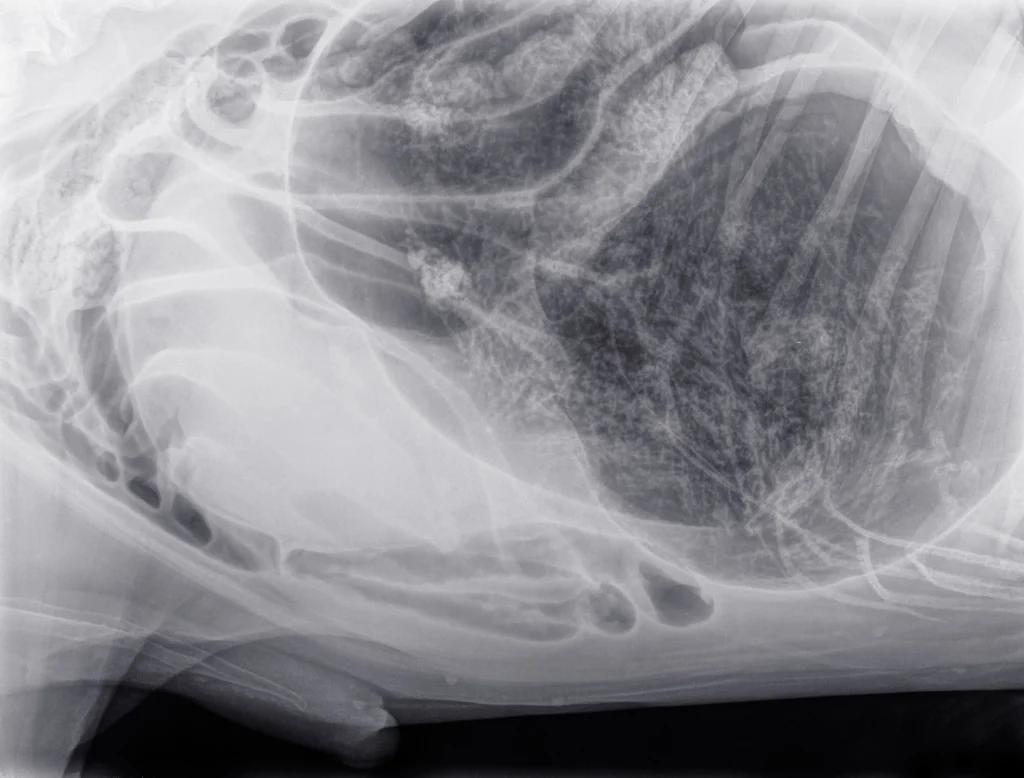

Radiologia

Le radiografie digitali permettono di ottenere diagnosi accurate sia in ambito ortopedico che per le patologie dei tessuti molli. La nostra struttura è dotata di un’unità radiologica digitale avanzata ed è autorizzata all’esecuzione di radiografie ufficiali per il controllo della displasia di anca e gomito, oltre che per la diagnosi di patologie genetiche ed ereditarie nei piccoli animali.